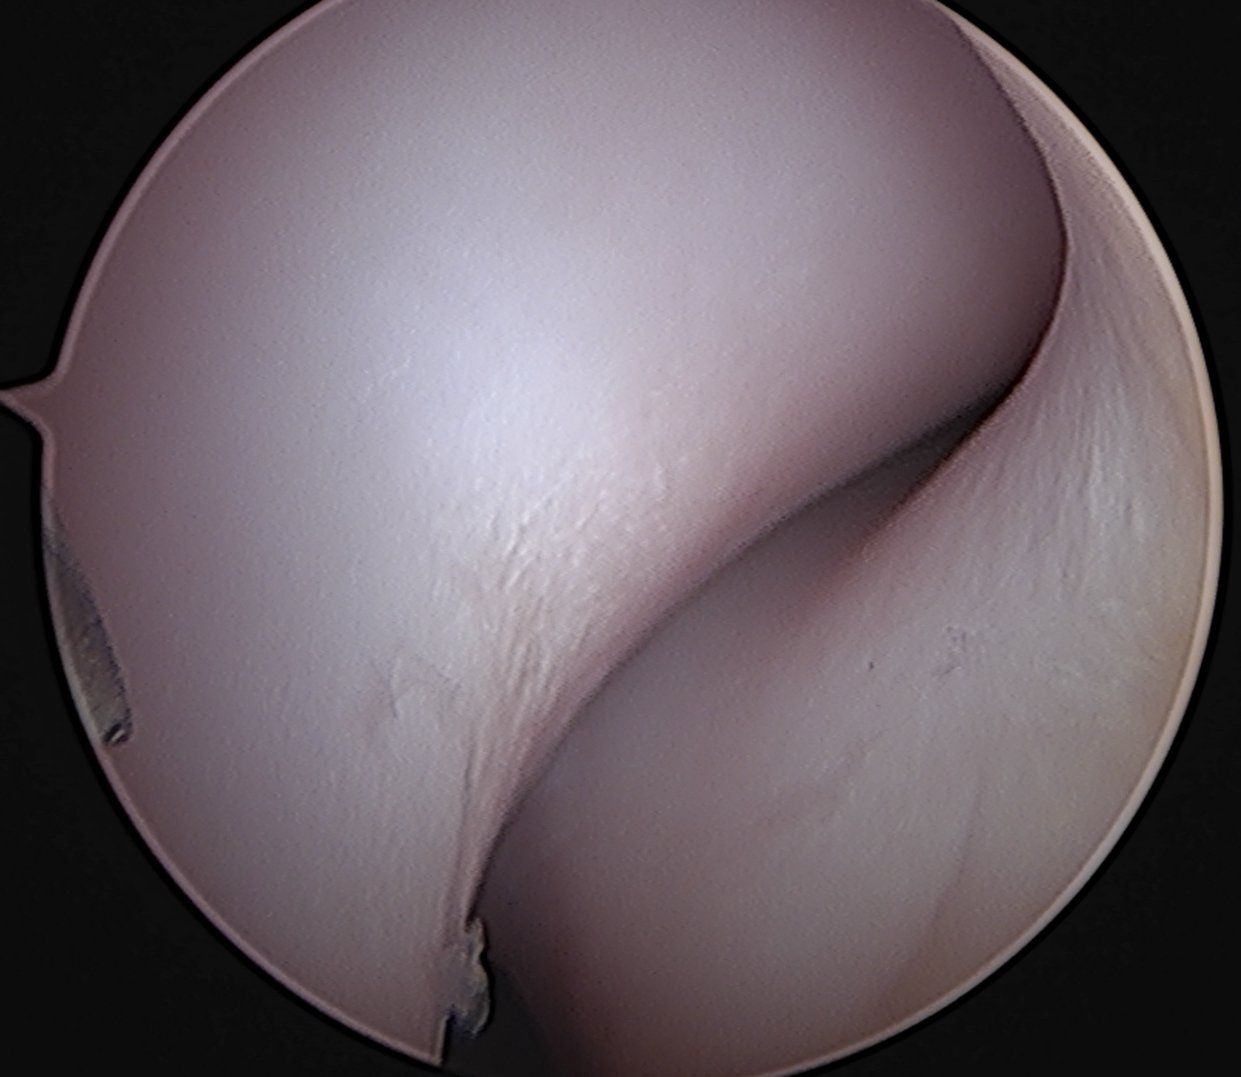

L'arthroscopie des deux coudes, réalisée sur la même anesthésie générale, a mis en évidence une lésion du processus coronoide médiale à droite comme à gauche, et surtout une érosion majeure et avancée du cartilage du compartiment médial. Cette atteinte est caractéristique d'une maladie du compartiment médial du coude, composante de la dysplasie du coude chez le chien. Le traitement sous arthroscopie consiste à tout d'abord réaliser un bilan lésionnel complet de la surface articulaire. Ensuite, si un fragment est présent, cette technique chirurgicale minimallement invasive permet de le retirer. Par ailleurs, une ostéotomie du processus coronoide médial peut également être réalisée sous contrôle visuel direct. Le pronostic après une arthroscopie du coude est bon dans la majorité des cas. Certains patients peuvent présenter une gène clinique et une boiterie au long terme en fonction du développement de lésions d'arthrose. Après le retrait du fragment dans le coude, cette articulation reste néanmoins abimée et nécessite par la suite une prise en charge de l'arthrose au long cours. L'arthroscopie permet donc à la fois de réaliser un bilan lésionnel complet de l'articulation, mais également de traiter la lésion lorsqu'il s'agit d'un fragment dans l'articulation.

Seule l'arthroscopie peut permettre d'orienter le propriétaire sur un pronostic et sur l'évolution arthrosique de son animal.

Légendes :

Images arthroscopiques du coude. L'incisure ulnaire (image 1) est normale. Un fragment détaché dans l'articulation est visible, associée à une lésion majeure de la surface articulaire sur l'image 2. L'image 3 montre le retrait du fragment à l'aide d'une pince. L'image 4 met en évidence une lésion d'OCD du condyle huméral médial et les lésions cartilagineuses associées.